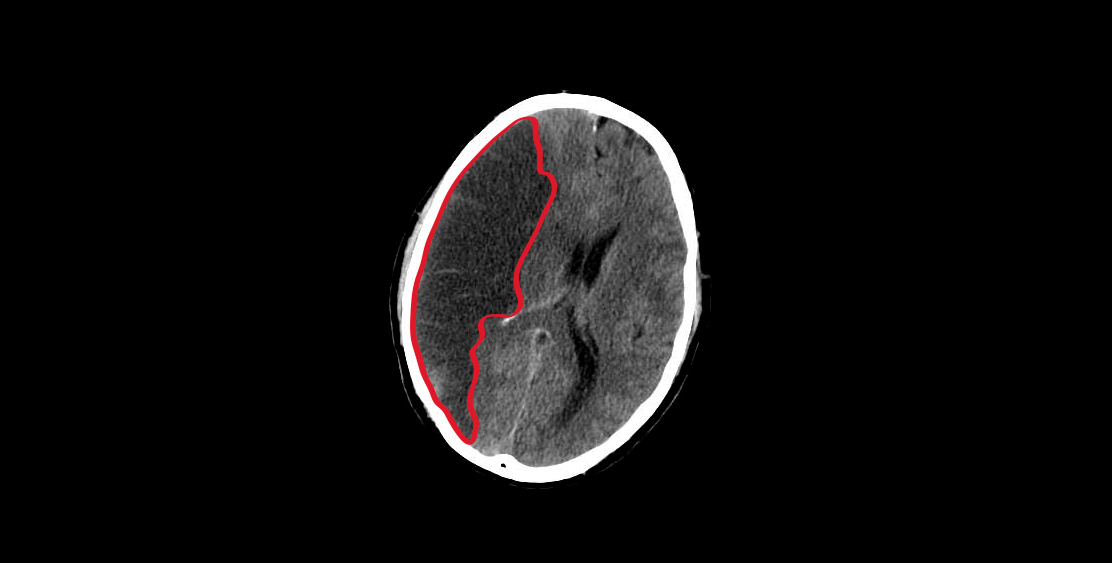

Hemorrhage

graphic of a brain with cerebral hemorrhage

Dr. Manuel Porras Bentacourt. (n. d.). Evento vascular cerebral (EVC). Consulted on the 31 of October of 2018 from http://neurochih.com/Inicio/evento-vascular-cerebral-evc/

A hemorrhagic cerebrovascular event (CVE) is a condition that occurs when a blood vessel in the brain breaks down. The blood runs out and can irritate or hurt the brain tissue or cause damage by pushing against neighboring areas. Then you can see a diagram of each one with its corresponding subcategories and characteristics.

Intracerebral hemorrhage occurs when the rupture of a brain vessel results in spontaneous bleeding within the cranial cavity; They are classified according to their location.

Intraparenchymal hemorrhage (HIP) is a blood collection within the brain parenchyma, produced by vascular rupture, whose shape, size, location and etiology is variable. The clinical manifestations of HIP are consistent with the location of the hematoma and depending on the underlying cause of the hemorrhage, the HIP is divided into primary or secondary.